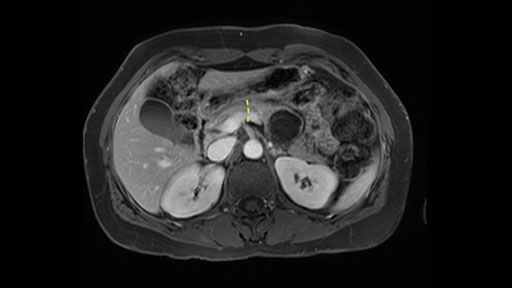

In reviewing this patient’s CT scan, first of all, the lesion is again cystic with a very thin wall. I anticipate that it will be delicate and potentially friable. And therefore the risk of rupture exists and we need to be very careful in how we handle the pancreas and the tumor throughout the procedure.

The lesion itself is quite adjacent to and abuts the splenic vein and therefore we need to anticipate that these two structures will be intimately related and possibly impossible to separate between the two.